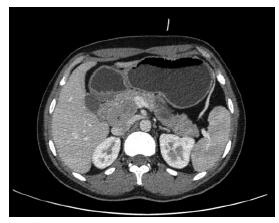

全组术前空腹血糖及血清癌胚抗原、糖类抗原199、糖类抗原125、糖类抗原242、糖类抗原724、甲胎蛋白均在正常值范围。1例神经特异性烯醇化酶水平升高(52.6 μg/L),1例组织多肽特异性抗原水平升高(148.5 U/L)。50例患者术前均行上腹部超声及CT或MR检查。超声表现为:胰腺或腹膜后类圆形低回声实性占位,肿瘤大小为10.7 cm×9.4 cm×7.8 cm,部分病变呈中央无回声的囊实性病变,有包膜;病变与周围血管界限清晰(图 1)。CT示:胰腺或腹膜后的类圆形囊实性低密度占位性病变,边界清楚,周边部分钙化;增强后肿瘤周边及实性区域呈不同程度强化,部分囊实性相间区域可见附壁结节,而囊性部分无强化(图 2,3)肿瘤大小为4.7 cm×3.0 cm;CT血管造影(CTA)示:未见周围血管受侵改变。MR示:病变内部有出血、囊性变。